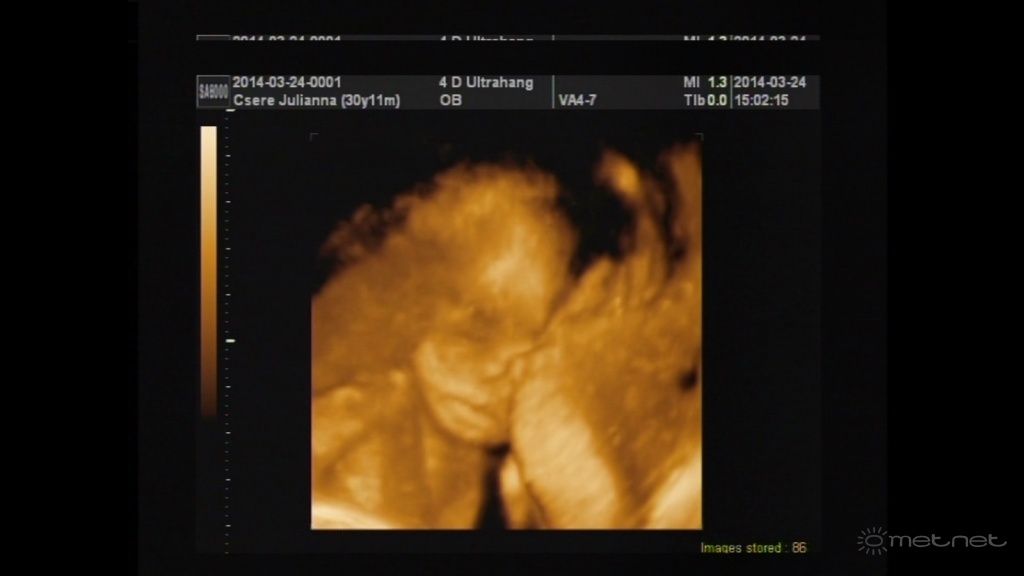

Leírás: Kislányom a 4d-s ultrahangon...